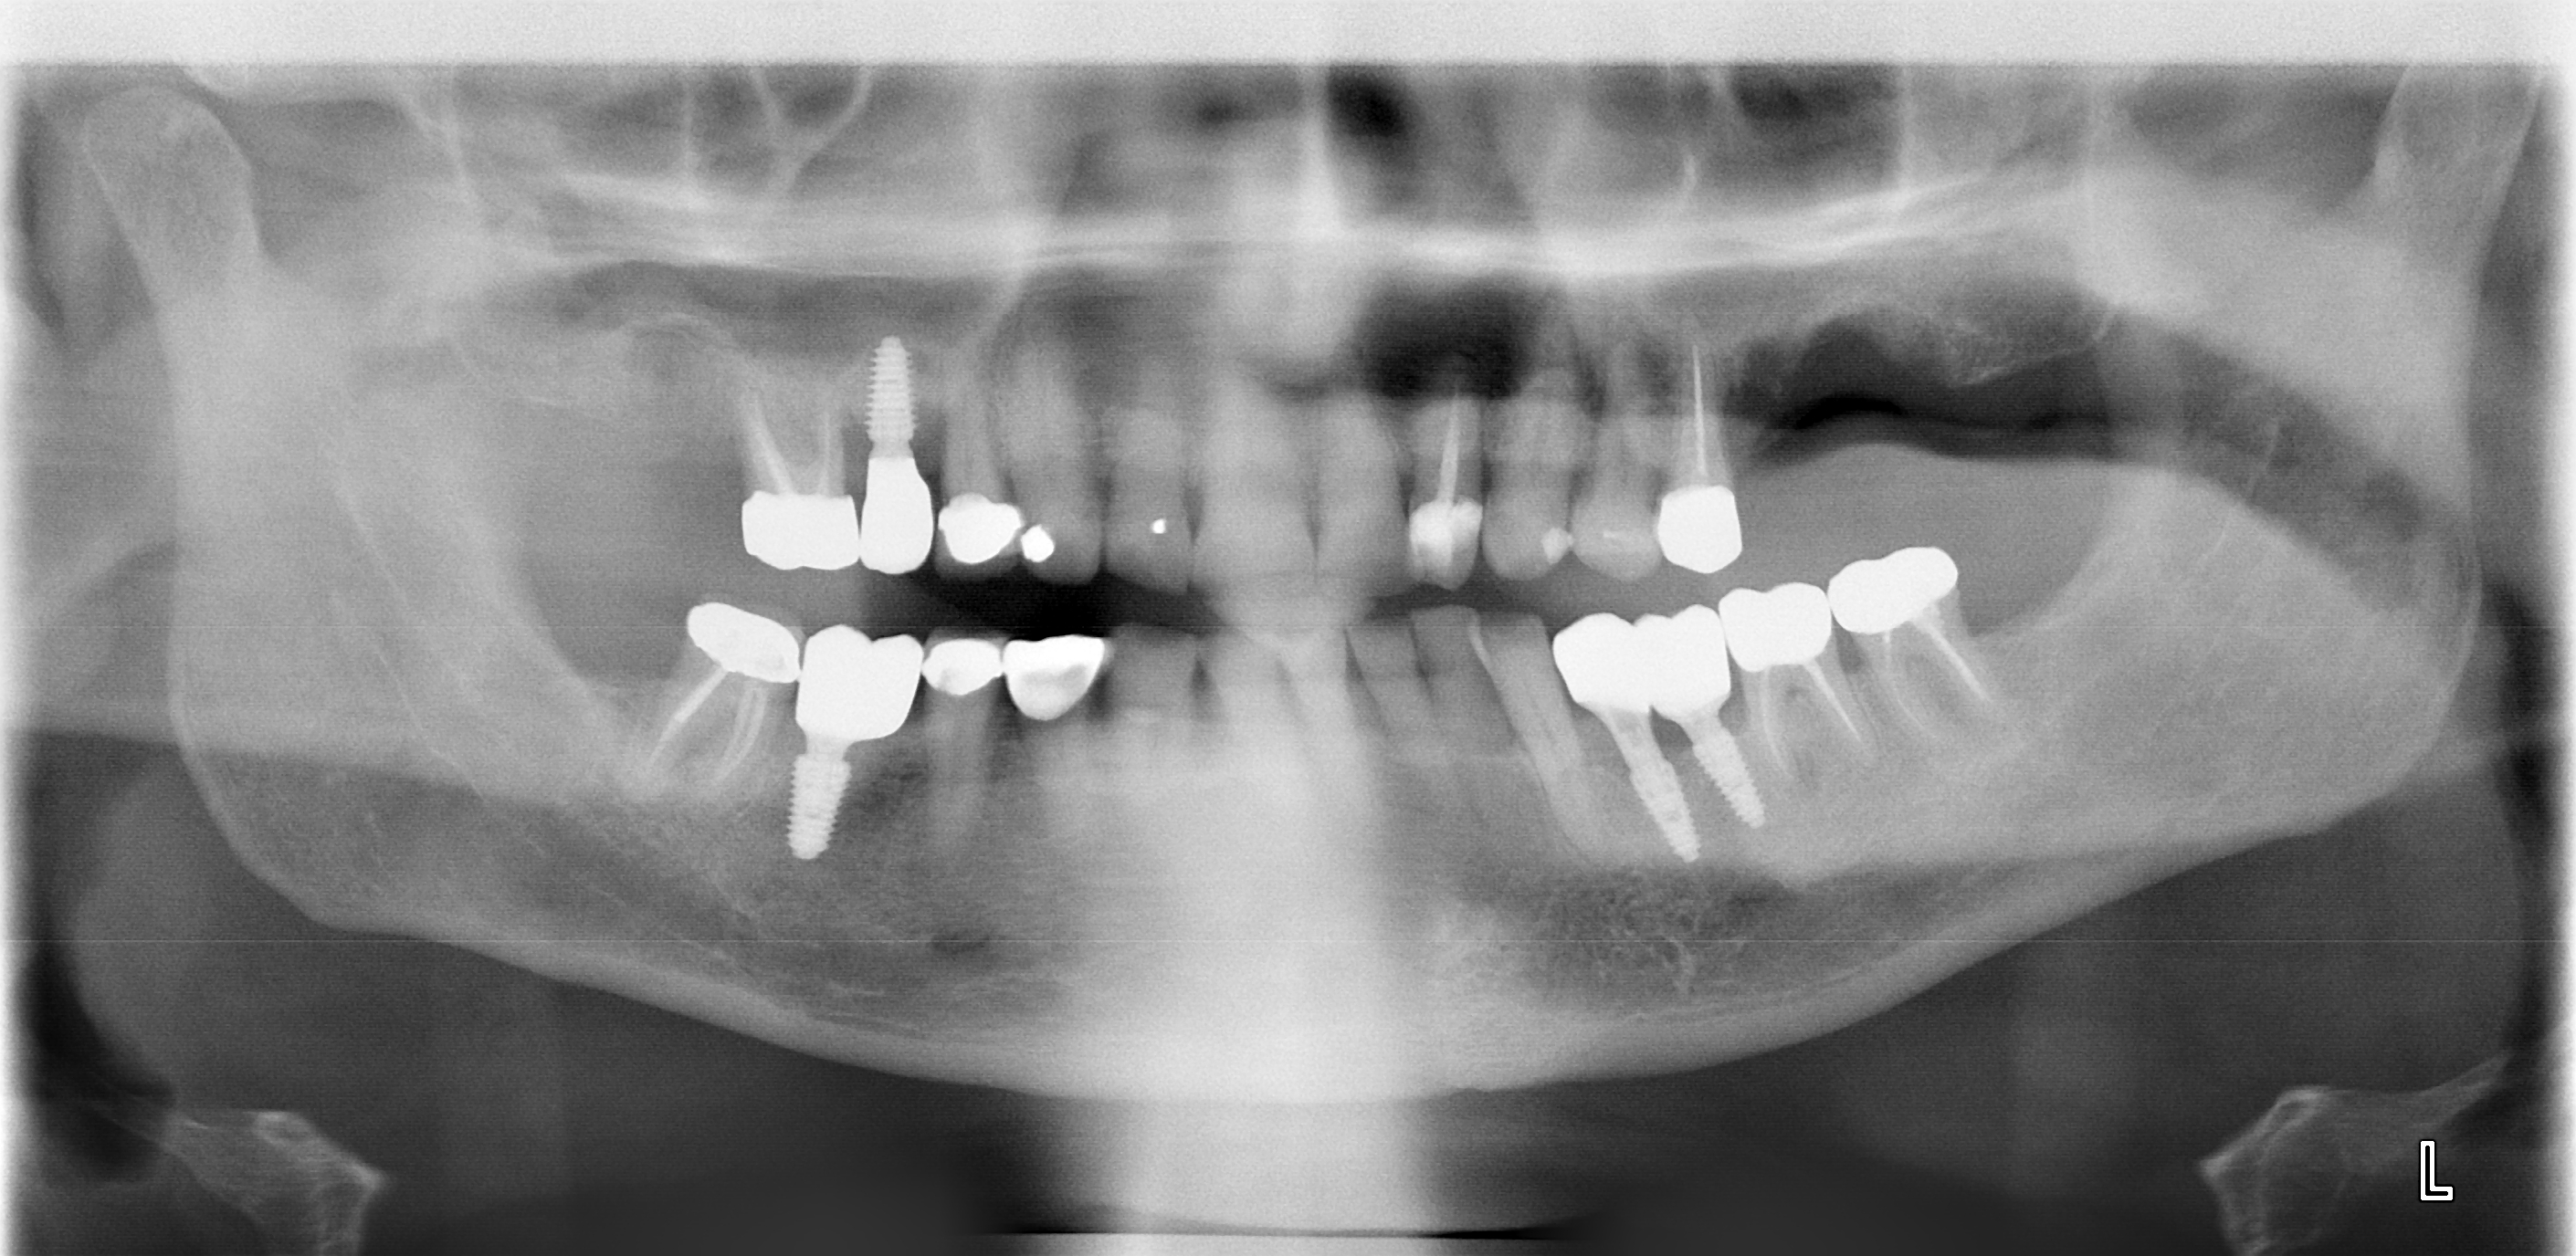

I go the dentist for final fitting of the implant that replaces the molar that was untimely ripped in London earlier this year.